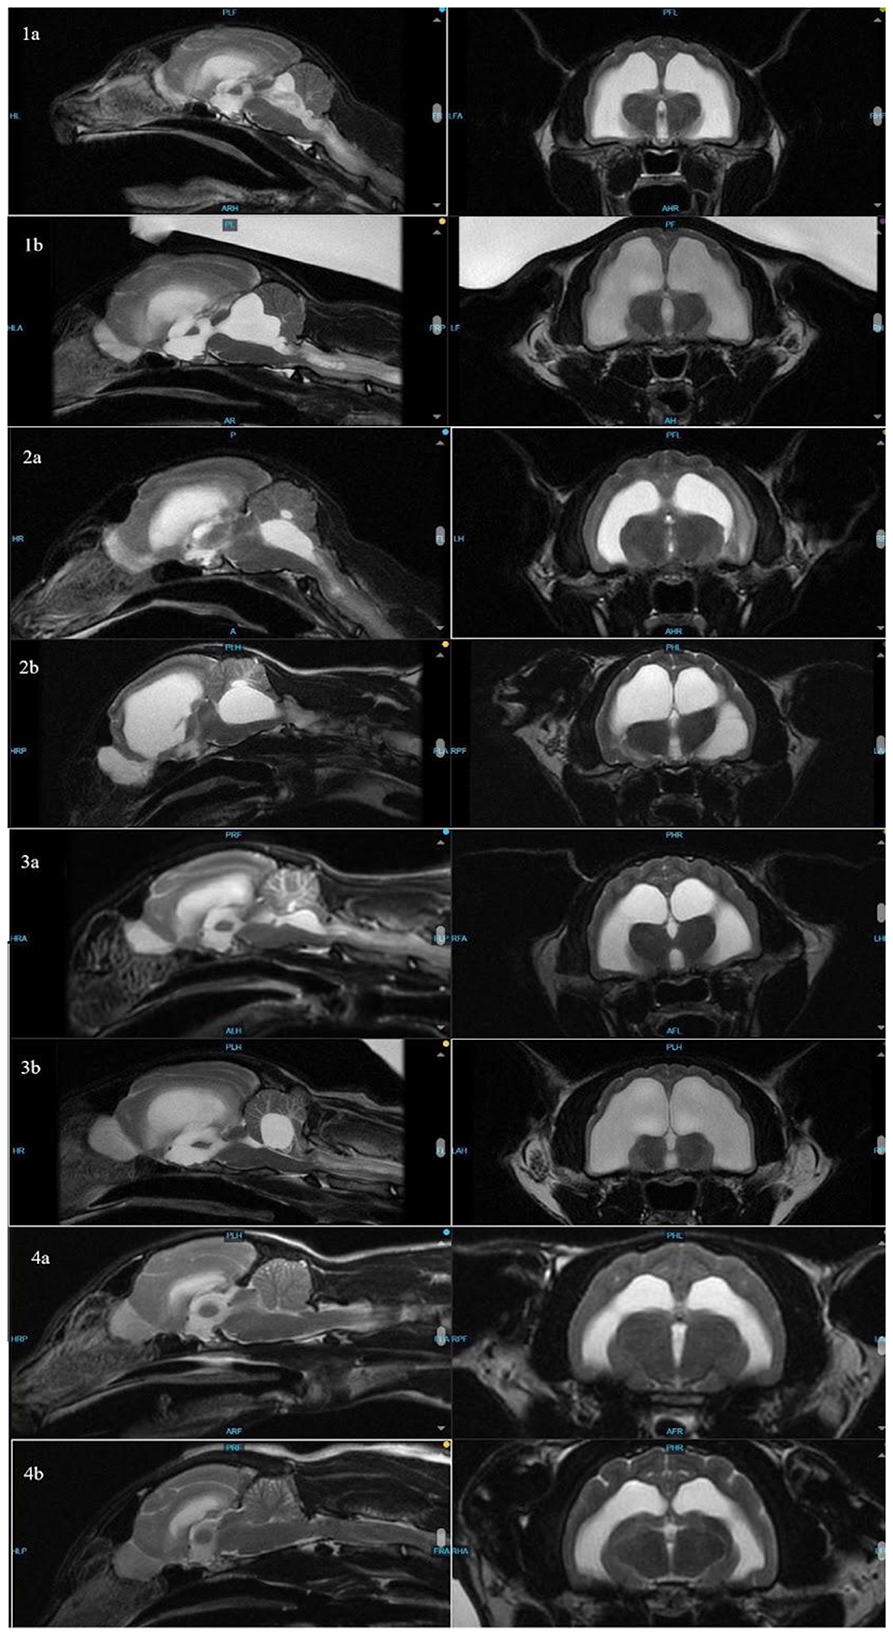

The cat was re-presented (aged 31 months) due to vestibular signs 13 months later. On examination, the cat was noted to have a mild left head tilt, decreased postural reactions on the right side, and pronounced vestibular ataxia. Repeat brain MRI showed markedly progressive hydrocephalus with no evidence of active inflammation (Figure 1). Due to progressive hydrocephalus and declining neurologic status, a ventriculoperitoneal shunt (VPS) was recommended. A Codman programmable VPS, with pressure set at 100 cm H2O (centimeters of water), was placed in the right lateral ventricle without complication; during surgery, CSF was sampled and submitted for analysis and Feline Coronavirus (FCoV) polymerase chain reaction (PCR). CSF collected was not sufficient for fluid analysis; cytology showed no evidence of inflammation. FCoV PCR was negative. The cat was discharged 2 days following shunt placement. At the time of discharge, he remained ataxic but was able to ambulate. He was re-evaluated 2 weeks after shunt placement, at which time he was noted to have mild vestibular ataxia, a subtle left head tilt, and subtle right-sided postural deficits. He presented 3 months post-shunt placement for his final recheck; the only neurologic deficit noted was equivocal vestibular ataxia. Telephone communication with the client 1 year after shunt placement indicated he was doing well at home, and he is alive at the time of writing.

Figure 1

MRI scans showing sagittal and axial views of a brain in different slices. The images are labeled 1a, 1b, 2a, 2b, 3a, 3b, 4a, and 4b. Each set presents detailed imaging of brain structures, with variations in tissue differentiation and contrast in each row.

Figure 1. Sagittal (left) and transverse (right) images of cats 1–4 to compare ventricle sizes and hydrocephalus at time of FIP diagnosis (a) and re-presentation (b).

At 26 months old, the cat was presented through the emergency department for concerns of recurrence of FIP based on a week-long history of progressive vestibular ataxia. Prior to transfer to neurology, he was given a single dose of GS-441524 (10 mg/kg) due to concern of relapse. Neurologic examination showed positional vertical nystagmus, decreased postural reactions in the left thoracic limb, and falling to the right. The cat was non-ambulatory due to vestibular ataxia. Repeat brain MRI showed progressive hydrocephalus (Figure 1). CSF was not collected due to cerebellar herniation through the foramen magnum. Initially, the owners opted for medical management with dexamethasone (0.1 mg/kg/day) and omeprazole (10 mg/kg BID), but his neurologic status declined when the dexamethasone was tapered.

All affected cats were presented 13–14 months after completing GS-441524 treatment. The neurologically normal cat had a repeat MRI 15 months after treatment. All cats showing vestibular signs had resolution or near resolution of ventriculitis based on pre- and post-contrast sequencing and progressive hydrocephalus based on comparison of pre- vs. post-treatment MRIs, including brain height to lateral ventricle height ratios (14). Brain height to lateral ventricular ratio has been used to estimate cerebral ventricle volume in cats and has been used to quantify feline hydrocephalus (14, 15). Although the caseload is too limited to determine statistical significance, this ratio, when applied to these cases, does suggest progressive ventriculomegaly in affected cats (Table 2).

The distribution of fluid in the ventricles, with the disproportionate enlargement of the fourth ventricle, would explain clinical signs of vestibular dysfunction seen in these cases due to compression of the cerebellum and brainstem. While lateral ventricle size and its relation to brain height has been studied to evaluate clinical hydrocephalus in cats, there is a paucity of veterinary literature classifying fourth ventricular size, especially in cats (14). In dogs, although the size of the fourth ventricle is found to be statistically different between hydrocephalus and ventriculomegaly groups, it is suggested that body mass may affect size of the fourth ventricle (24). Individually, each affected cat in this series presented with increased size in all ventricles, including, most dramatically, the fourth ventricle. In contrast, Case 4 showed no discernible enlargement of the fourth ventricle pre- or post-treatment (Figure 2). While there is no standardized ratio or measurement that has been proven to characterize the size or volume of the fourth ventricle in cats, in all affected cats, the fourth ventricle displays progressive dilation.